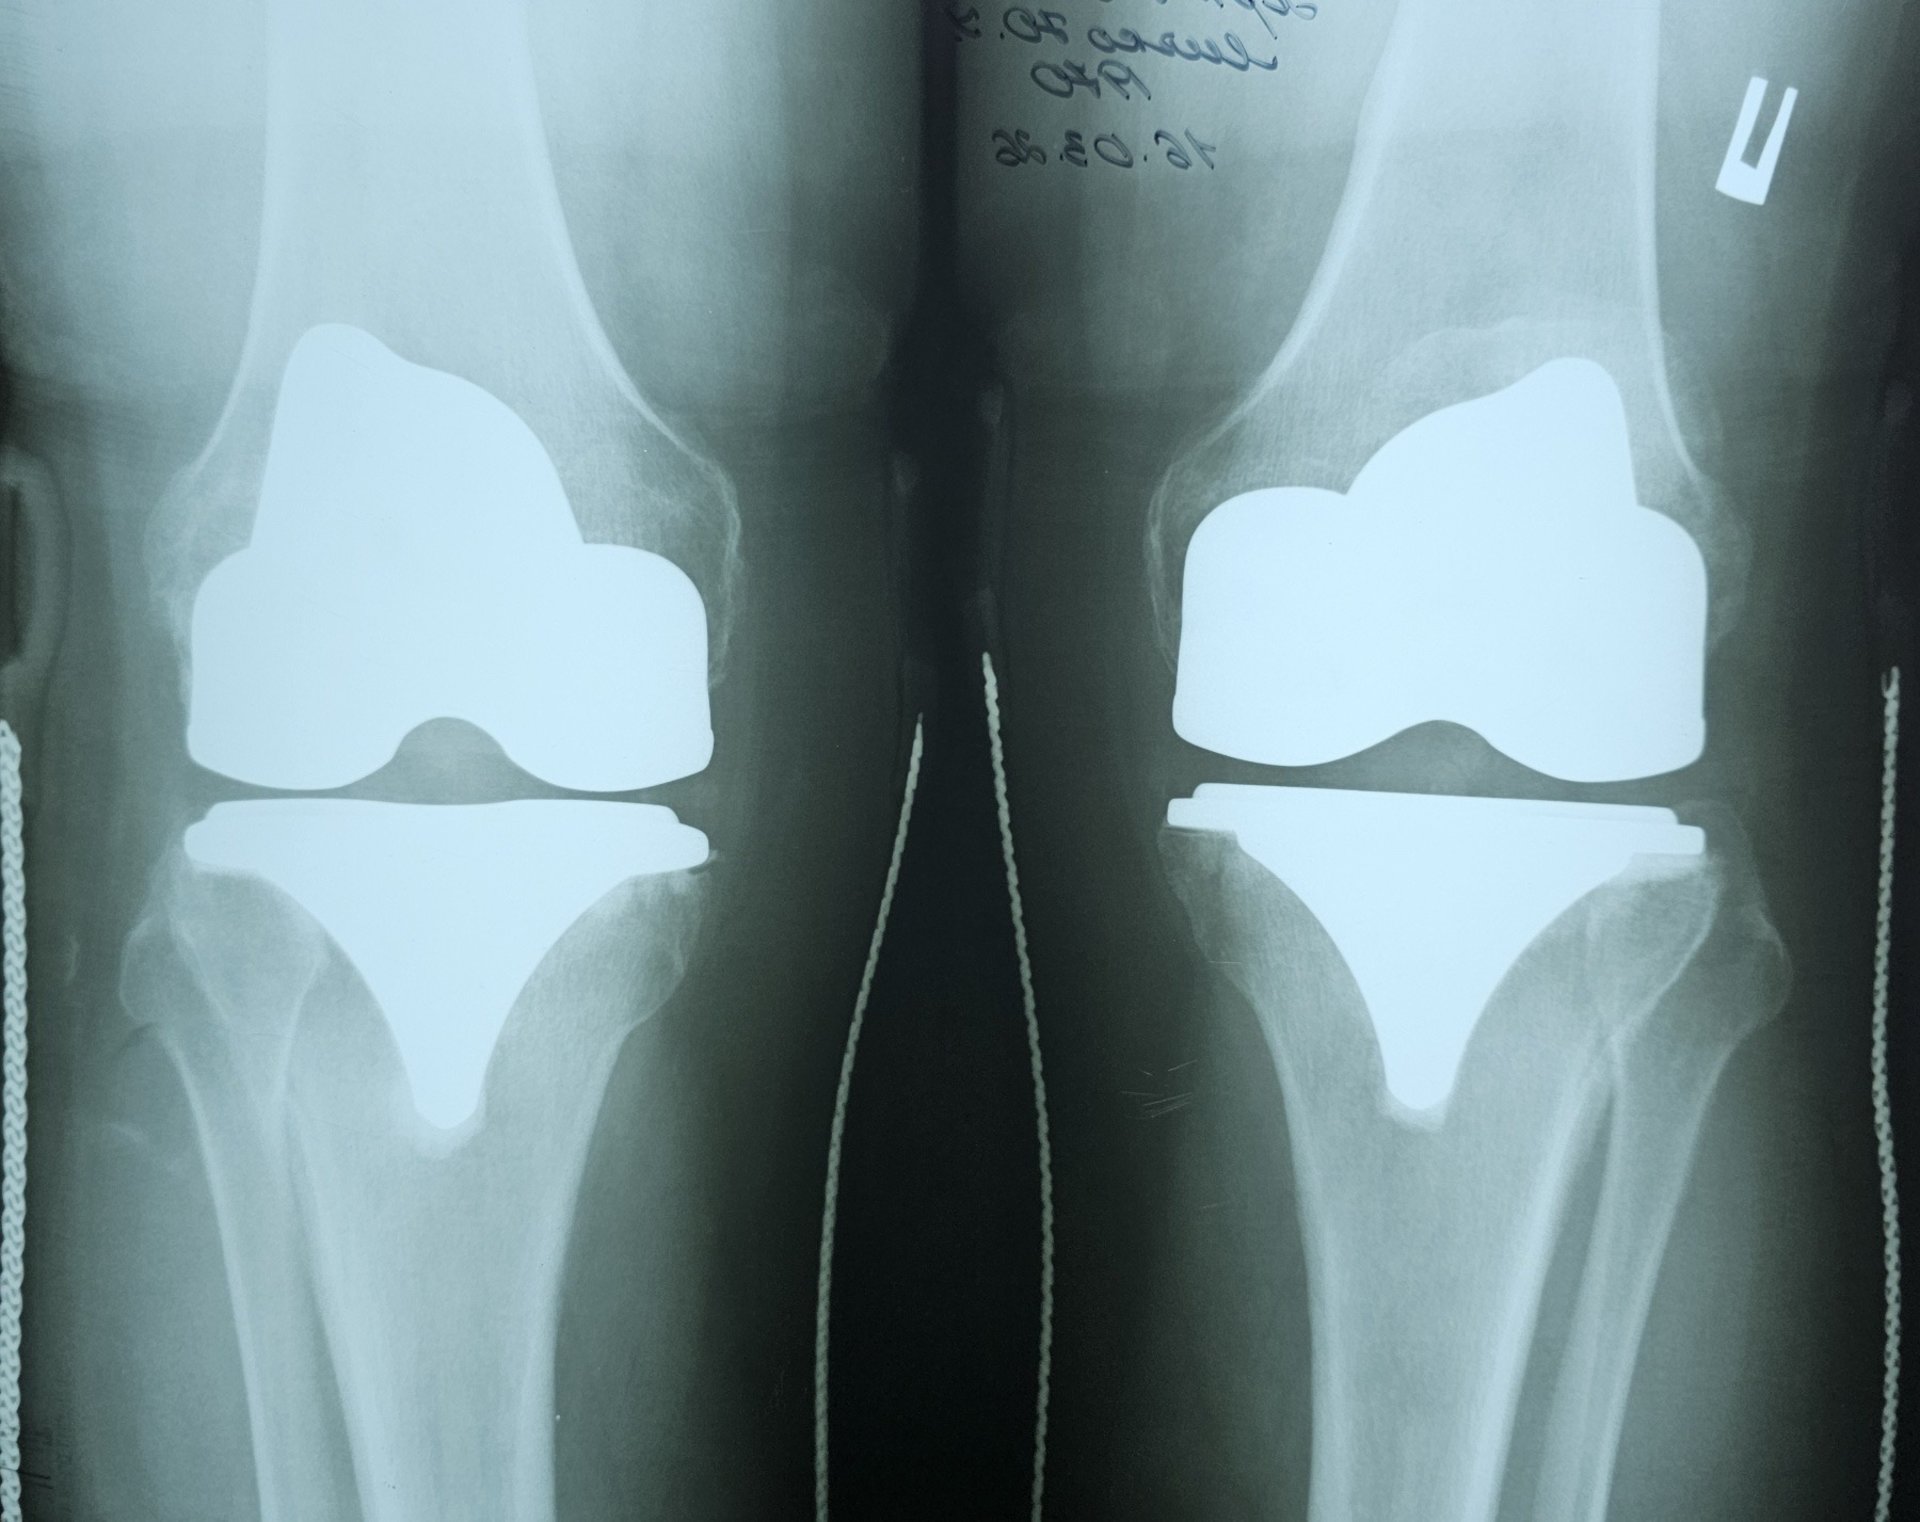

«Хворому провели тотальне цементне ендопротезування лівого і правого колінних суглобів. Післяопераційні періоди проходили без ускладнень. У задовільному стані пацієнта виписали в реабілітаційне відділення ЗОКЛ ім. А.Новака, де він пройшов курс повноцінного відновно-реабілітаційного лікування», – розповів Іван Дорогій.

Після операції та курсу реабілітації стан пацієнта значно покращився, що дозволило йому відновлювати рухливість і повернутися до повсякденного життя.